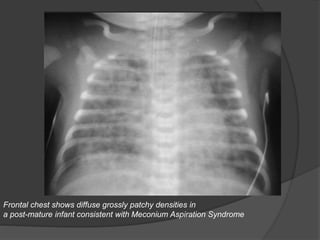

MECONIUM ASPIRATION SYNDROME

Radiography

•Imaging findings Bilateral diffuse grossly patchy / coarse opacities (atelectasis and

consolidation)

•Rope-like perihilar densities

•Hyperinflation of lungs

•Areas of emphysema (air-trapping)

•Spontaneous pneumothorax and pneumomediastinum

•25% requiring no therapy

•Small pleural effusions (20%)

•Rapid clearing usually within 48 hours

Frontal chest shows diffuse grossly patchy densities in

a post-mature infant consistent with Meconium Aspiration Syndrome